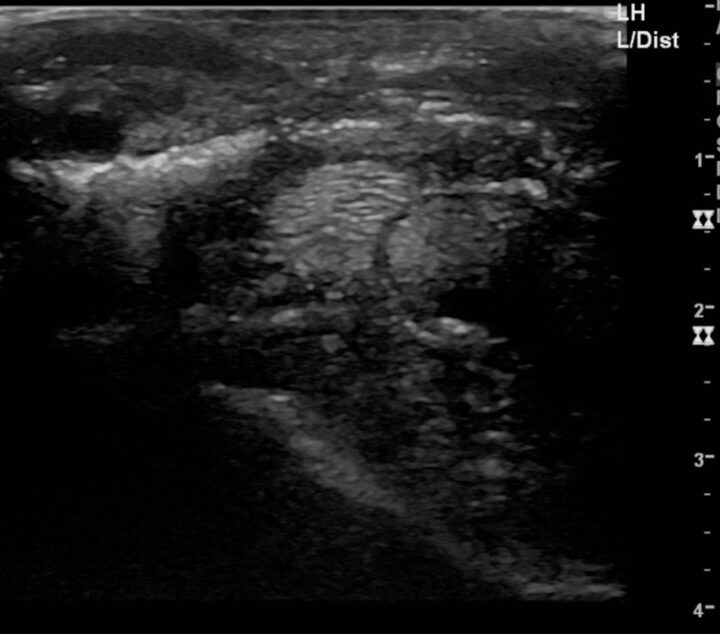

To accurately assess the depth, extension and size of acute wounds, clipping and cleaning are essential, particularly as the wound frequently extends further than anticipated before clipping (Figures 1 and 2). The use of radiographs and ultrasound can help determine involvement of, and damage to, underlying structures, demonstrate the presence of foreign bodies and give an indication of penetration of adjacent synovial structures. Gas within synovial structures may be observed as radiolucencies on radiographs (Figure 3) or hyperechogenicity on ultrasound scan, but they must be differentiated from superimposed subcutaneous gas/air within fascial planes (Figures 4 and 5).